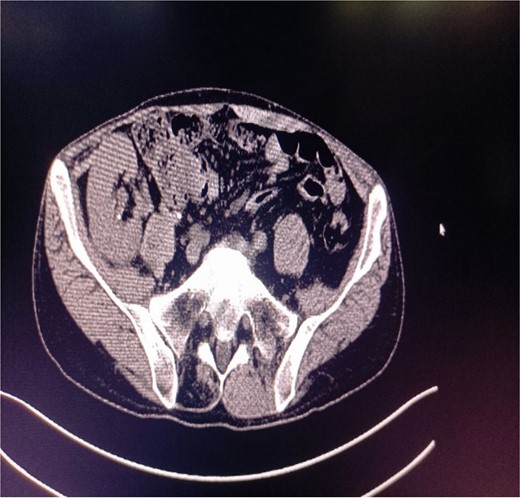

X-ray plain film showing multiple punctate stones in the right kidney area.

A 39-year-old man with kidney stones after kidney transplantation was admitted to our hospital on 29 November 2023. Eight years ago, he underwent a kidney transplant from a donor. Neither the donor nor the recipient had a history of kidney stones. The transplanted kidney was positioned in the right iliac fossa, and the patient had a successful postoperative recovery. However, a recent routine abdominal computed tomography (CT) scan revealed multiple stones in the transplanted kidney and bilateral in situ kidney atrophy. The stone was located in the lower calyx of the transplanted kidneys. Hydronephrosis was also observed. Kidney, ureter, and bladder radiographs showed multiple high-density speckles in the right kidney, the largest of which was ~0.5 cm in diameter. Physical examination (blood pressure, 147/91 mmHg; serum creatinine, 72.7 μmol/L; urea nitrogen, 5.1 mmol/L) revealed normal liver function, coagulation, and electrolytes. We suspected that these kidney stones were sizable and necessitated surgical intervention. Upon admission, pertinent examinations were conducted, and preoperative preparations were completed.